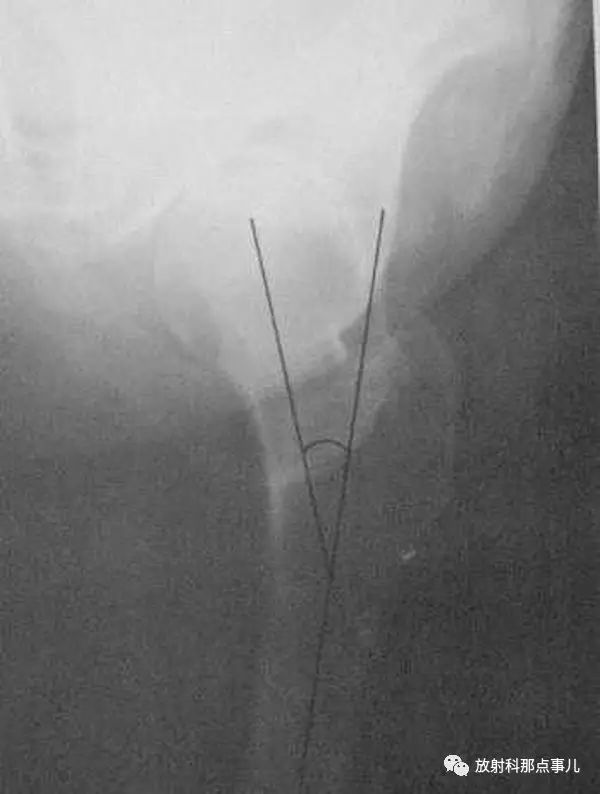

髋臼角

骨盆正位片上,两侧Y形软骨中心连线与髋臼上下缘连线所形成的夹角。正常值新生儿为30° ,1岁以后不应超过25° ,2岁时为20° ,成人为10° 。先天性髋关节脱位时髋臼变浅,髋臼角增大。(上图中角a)

髂骨角

髂前下棘和髋臼外上缘间连线与Y形软骨水平线的夹角。新生儿为55° ,正常值范围在43° ~67° ,角度减小提示异常,如骨质软化症。(上图中角b)